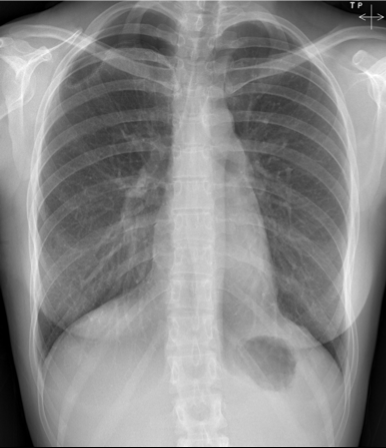

Pathology (in right image)?

Cardiomegaly